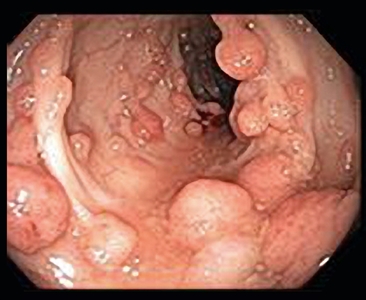

By 1900, several reports had demonstrated that patients with a large number of polyps (later subclassified as adenomas) were at very high risk of CRC and that the pattern of transmission in families was autosomal dominant. In the 20th century, the adenoma-to-carcinoma progression was confirmed, and FAP was recognized as the prototypical model for this progression.[11] Classic FAP is characterized by numerous (hundreds to thousands) adenomatous polyps in the colon and rectum developing after the first decade of life (refer to Figure 3).

Many polyps protrude from the inner lining of the colon.

Figure 3. Familial adenomatous polyposis is characterized by multiple (>100) adenomatous polyps in the colon and rectum developing after the first decade of life.